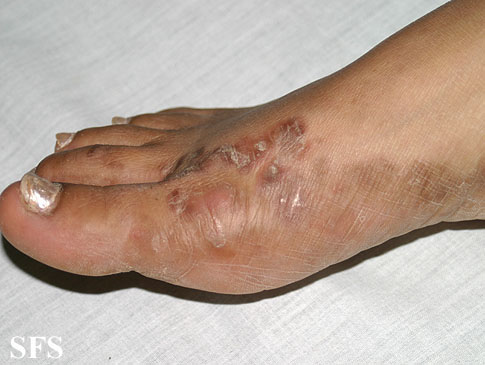

Genitalia Wart

condyloma acouminata